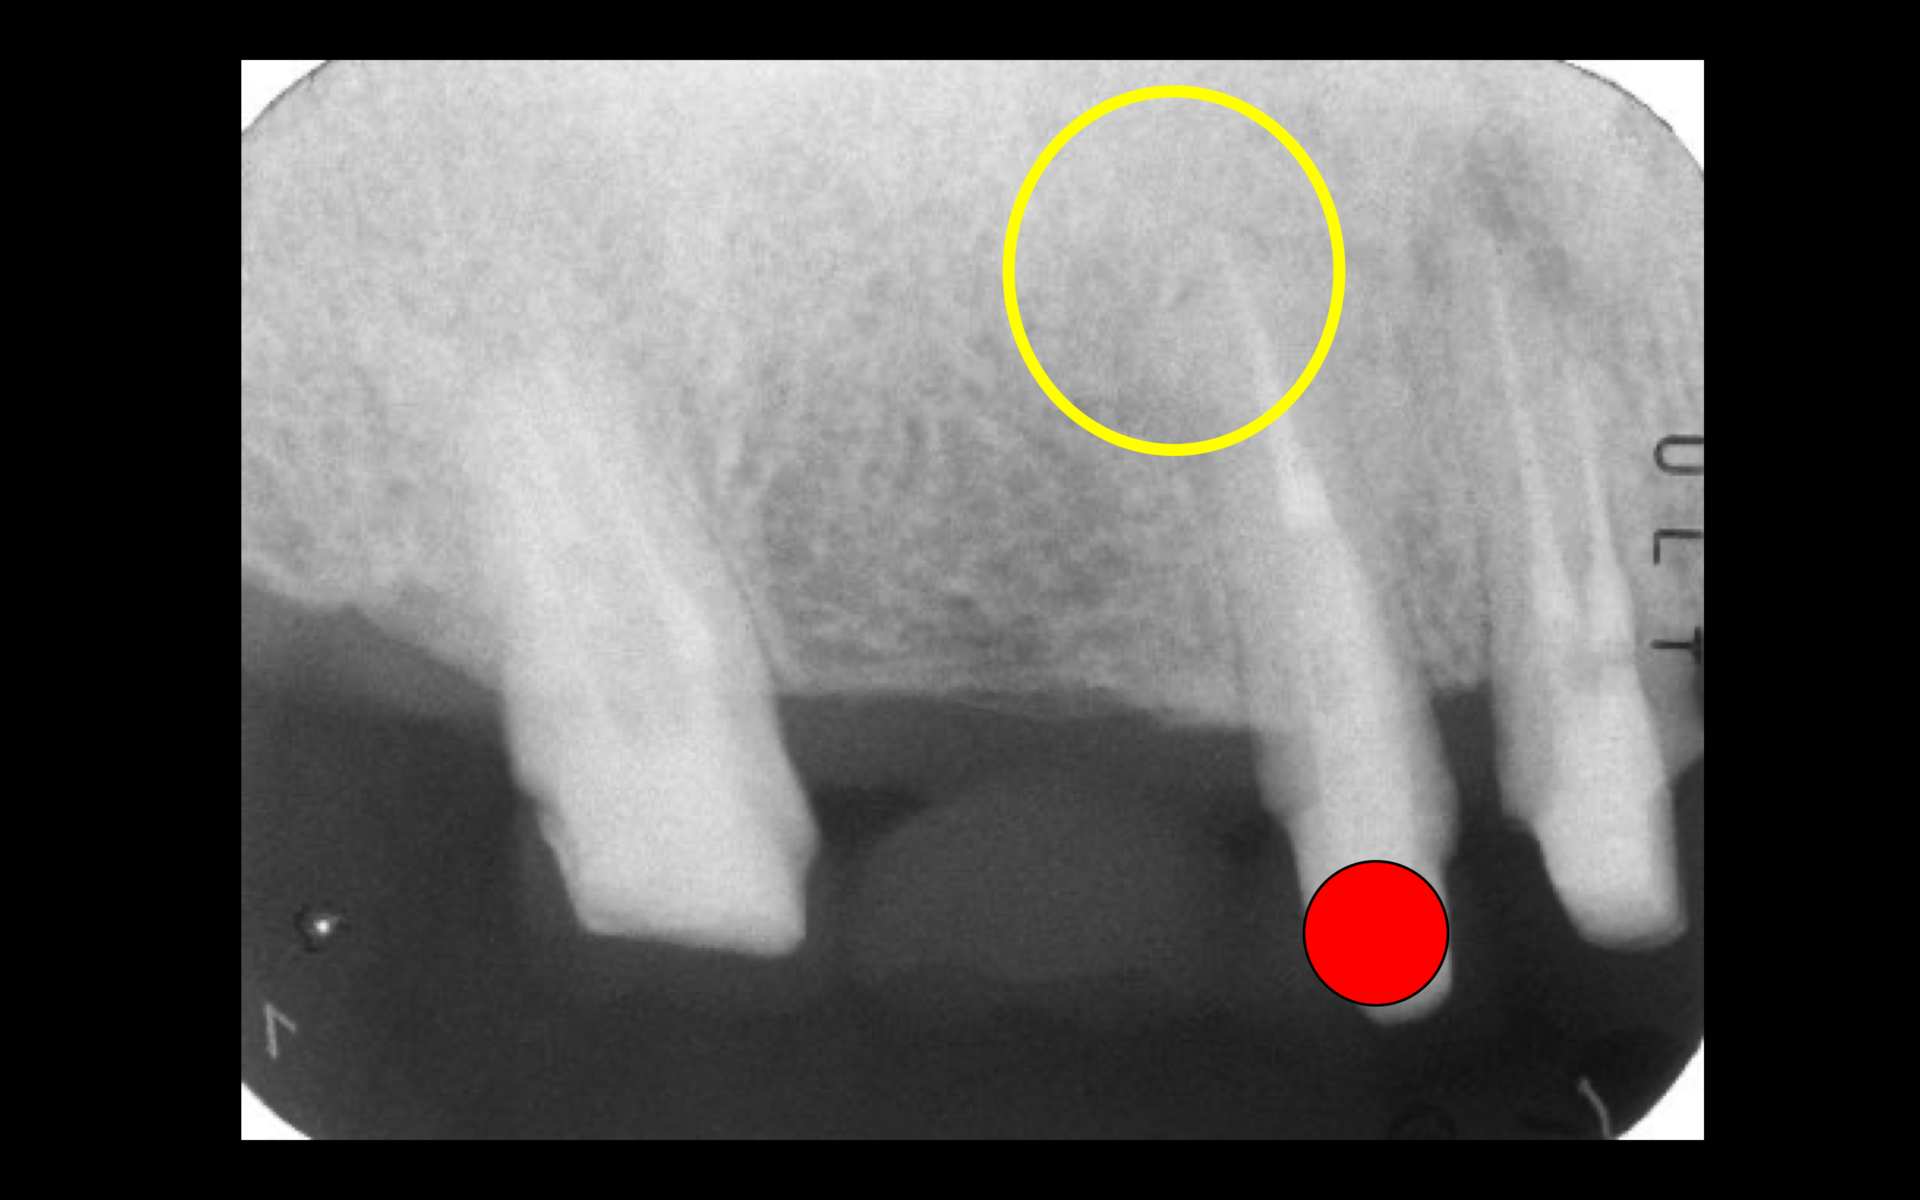

レントゲン所見より、黄色の円の中にある黒い部分が病変である。歯肉の腫れている原因は赤い点で記している上顎第二小臼歯の根尖病変であることが分かったため、精密根管治療を行うことになった。

精密根管治療1年後のレントゲン。主訴であった赤い点で記した第二小臼歯の根尖病変は消失し、骨が再生された(黄色の円の部分)